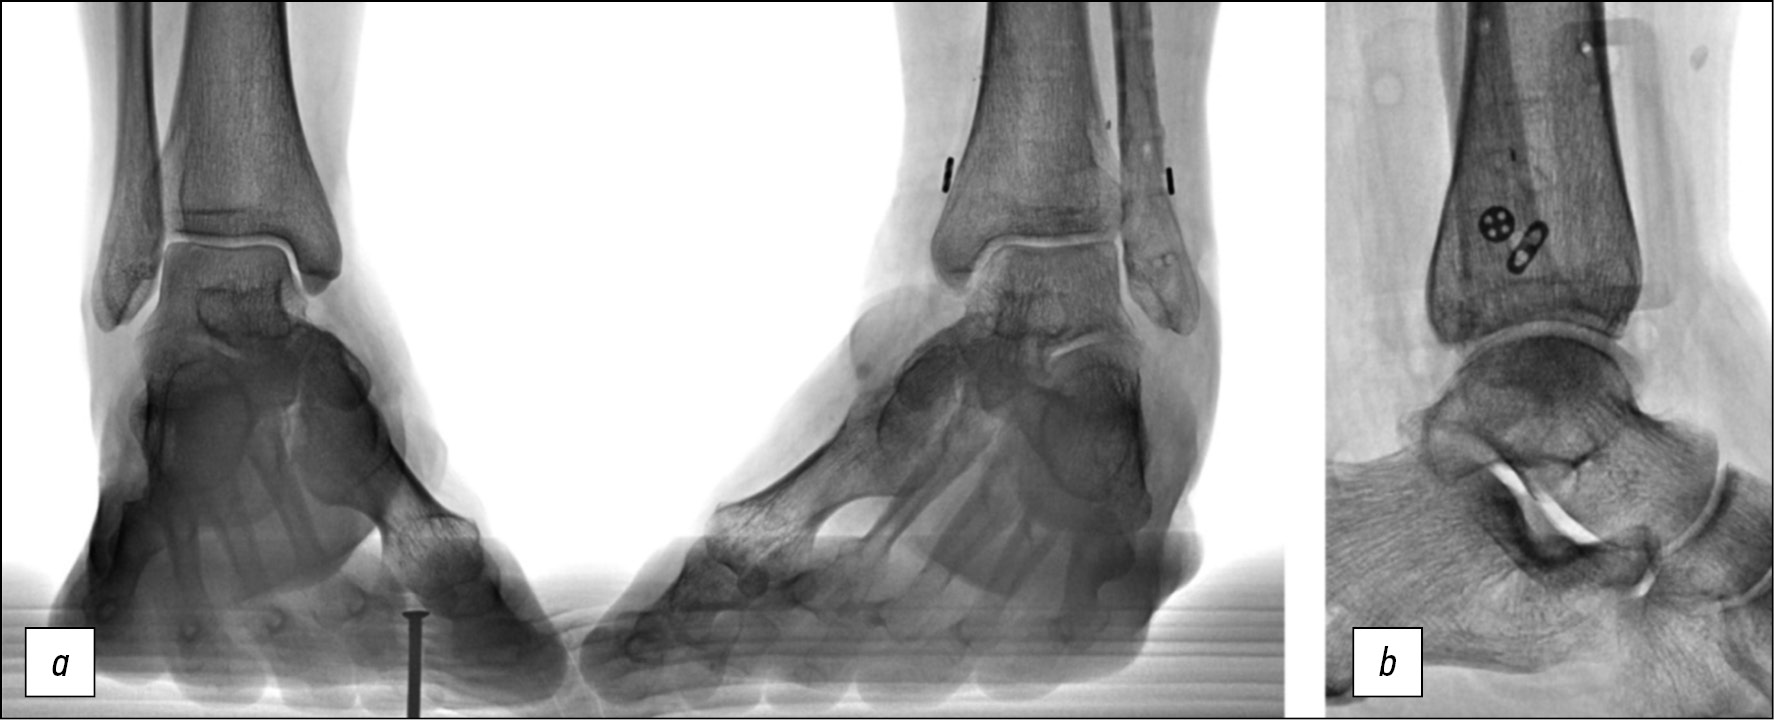

Послеоперационные рентгенограммы в прямой (рис. 9a) и боковой (рис. 9b) проекциях демонстрируют восстановление взаимоотношений в голеностопном суставе. Гониограммы (рис. 9c, d) и подограммы (рис. 9e, f) на 7-е сутки после операции — ходьбу без дополнительных средств опоры в условиях внешней фиксации, демонстрирующую наличие сниженного активного подошвенного сгибания стопы, незначительной асимметрии при равномерном распределении нагрузки на передний и задний отделы стопы оперированной конечности. Период госпитализации составил 9 дней, срок фиксации в аппарате Илизарова — 34 дня.

Рис. 9. a — рентгенограмма пациента П. после операции в прямой проекции, b — рентгенограмма в боковой проекции, c, d — гониограммы, e, f — подограммы

Fig. 9. Postoperative X-rays of patient P.: a — A-P-view, b — lateral view, c, d — gait analysis, e, f — computer podography

Рентгенограммы голеностопного сустава в прямой проекции с внутренней ротацией (стоя с нагрузкой) (рис. 10a, b) и боковой проекции (рис. 10c) демонстрируют восстановление взаимоотношений в голеностопном суставе, расположение продолговатой пуговицы кзади от межлодыжечной линии. Опороспособность оперированной конечности и объём движений в голеностопном суставе восстановлены.

Рис. 10. Рентгенограммы пациента П. после демонтажа аппарата Илизарова: a, b — в прямой проекции с внутренней ротацией, c — в боковой проекции

Fig. 10. X-rays of patient P. after Ilizarov fixator removal: a, b — mortise view, c — lateral view